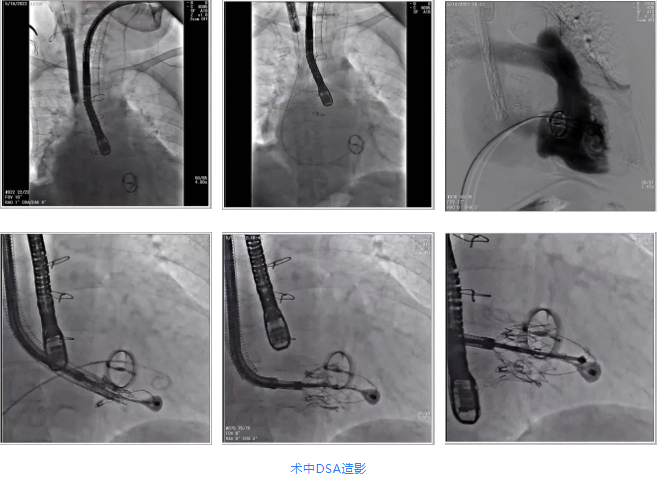

根據(jù)術(shù)前評(píng)估結(jié)果,郭應(yīng)強(qiáng)教授團(tuán)隊(duì)為患者量身定制了手術(shù)策略,決定使用LuX-Valve Plus經(jīng)血管三尖瓣置換系統(tǒng)開展手術(shù)治療。手術(shù)在全麻下進(jìn)行,采用經(jīng)右側(cè)頸靜脈入路,在經(jīng)食道超聲和DSA的指引下調(diào)整輸送器角度以達(dá)到正確位置,勾住前瓣后逐步釋放盤片,盤片打開后順利扎針,最終完成瓣膜植入,輸送器撤出。術(shù)后超聲提示人工三尖瓣同軸性良好,瓣架固定牢靠,無反流和瓣周漏,術(shù)后三尖瓣平均跨瓣壓差為1 mmHg。